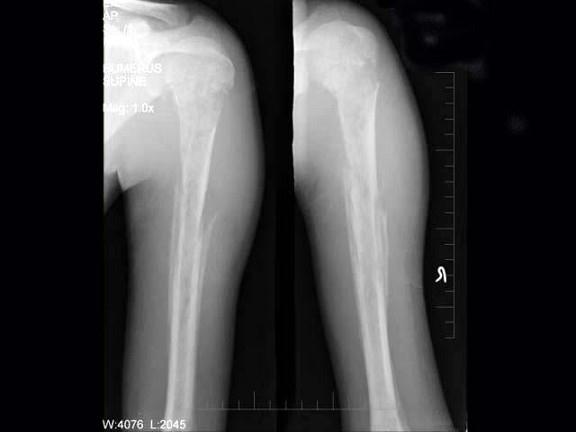

问题 男,15岁,畏寒,高热2周,摄片如图所示,下列诊断正确的是?(?)

选项 A.急性化脓性骨髓炎 B.慢性化脓性骨髓炎 C.溶骨性骨肉瘤 D.尤文肉瘤 E.以上均不正确

答案 A